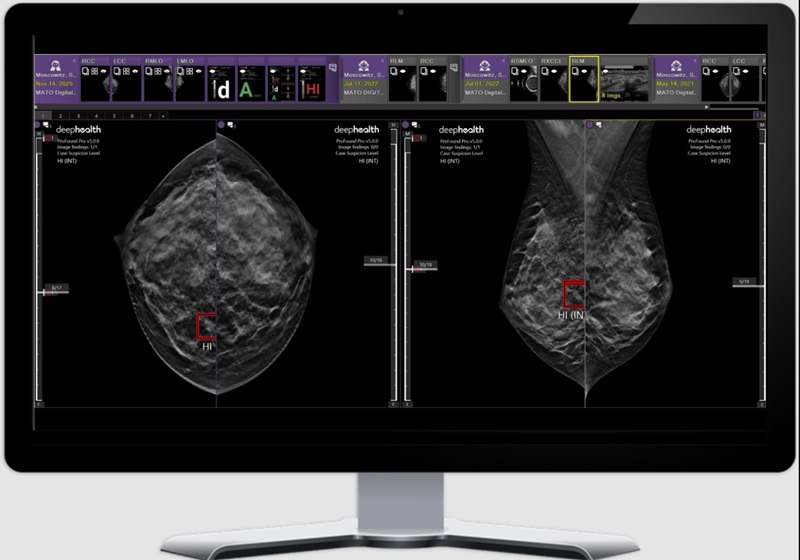

- GE HealthCare y Medtronic amplían su alianza con la integración de imágenes intraoperatorias.